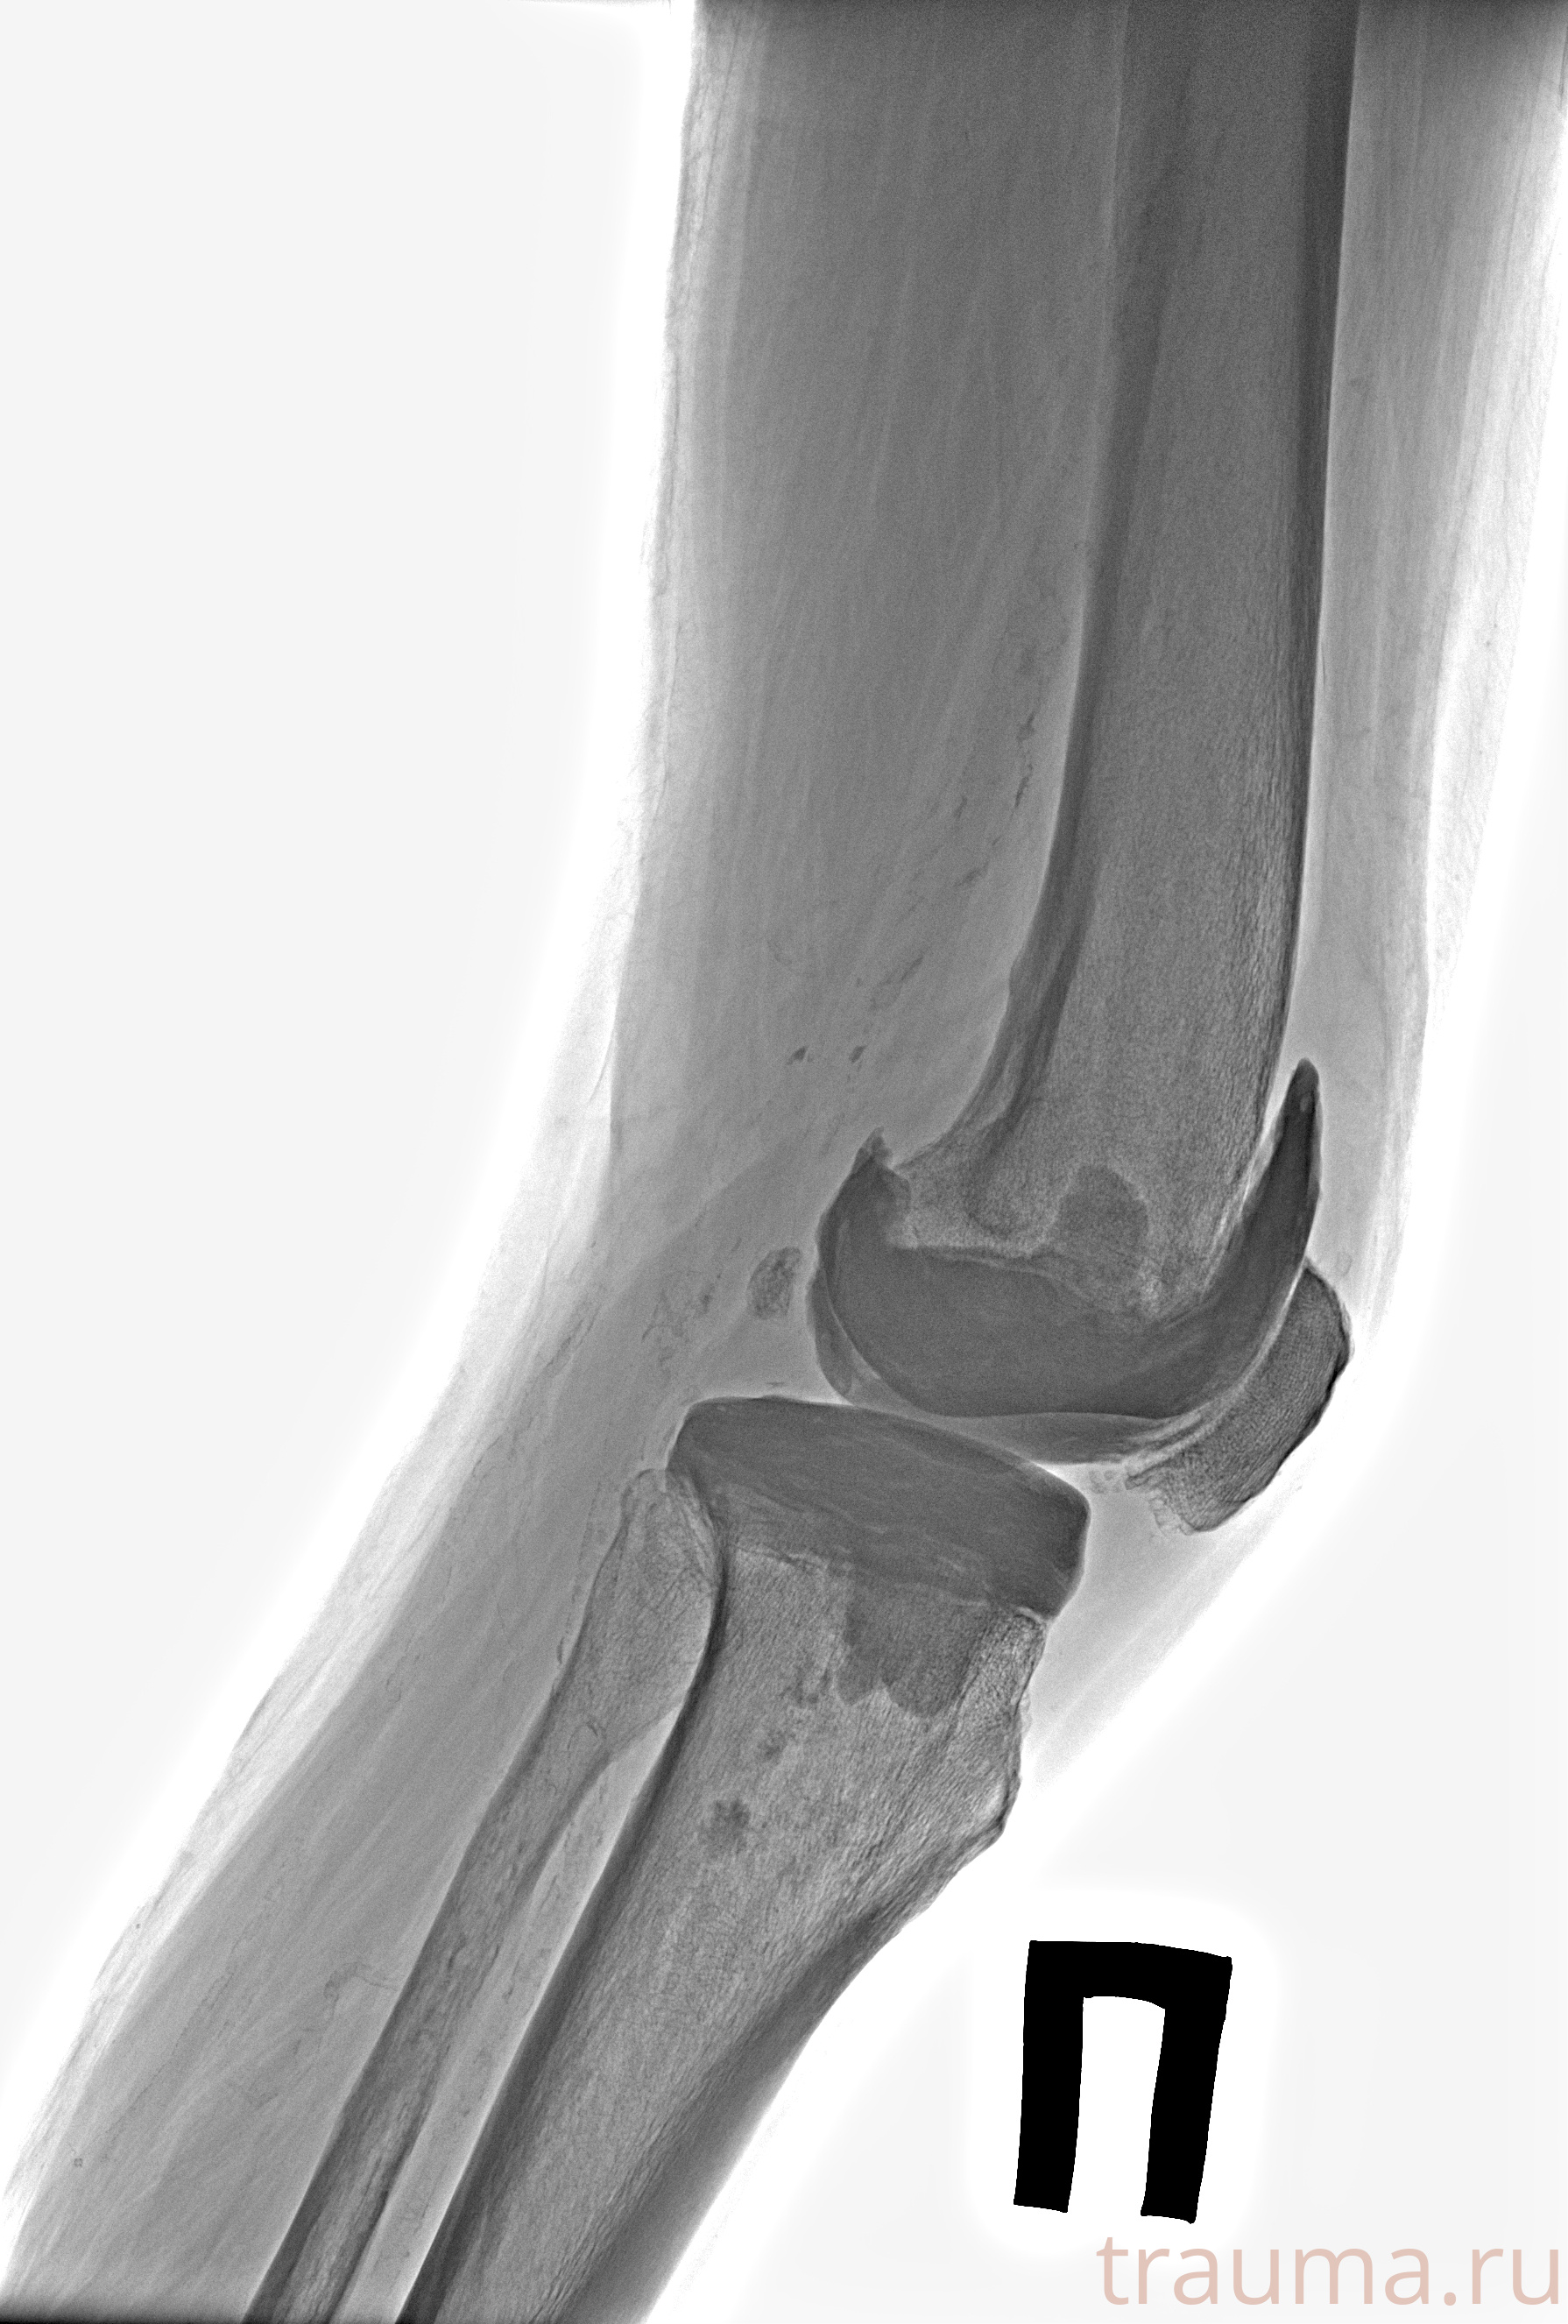

Рентген на дому: по вашему адресу приезжает врач-рентгенолог, травматолог-ортопед с мобильным рентгеновским аппаратом, проводит диагностику травмы или заболевания, делает необходимые рентгенограммы, дает рекомендации по дальнейшему лечению. Получить качественные снимки в домашних условиях возможно благодаря уникальной методике, разработанной МосРентген Центром для института  Склифосовского